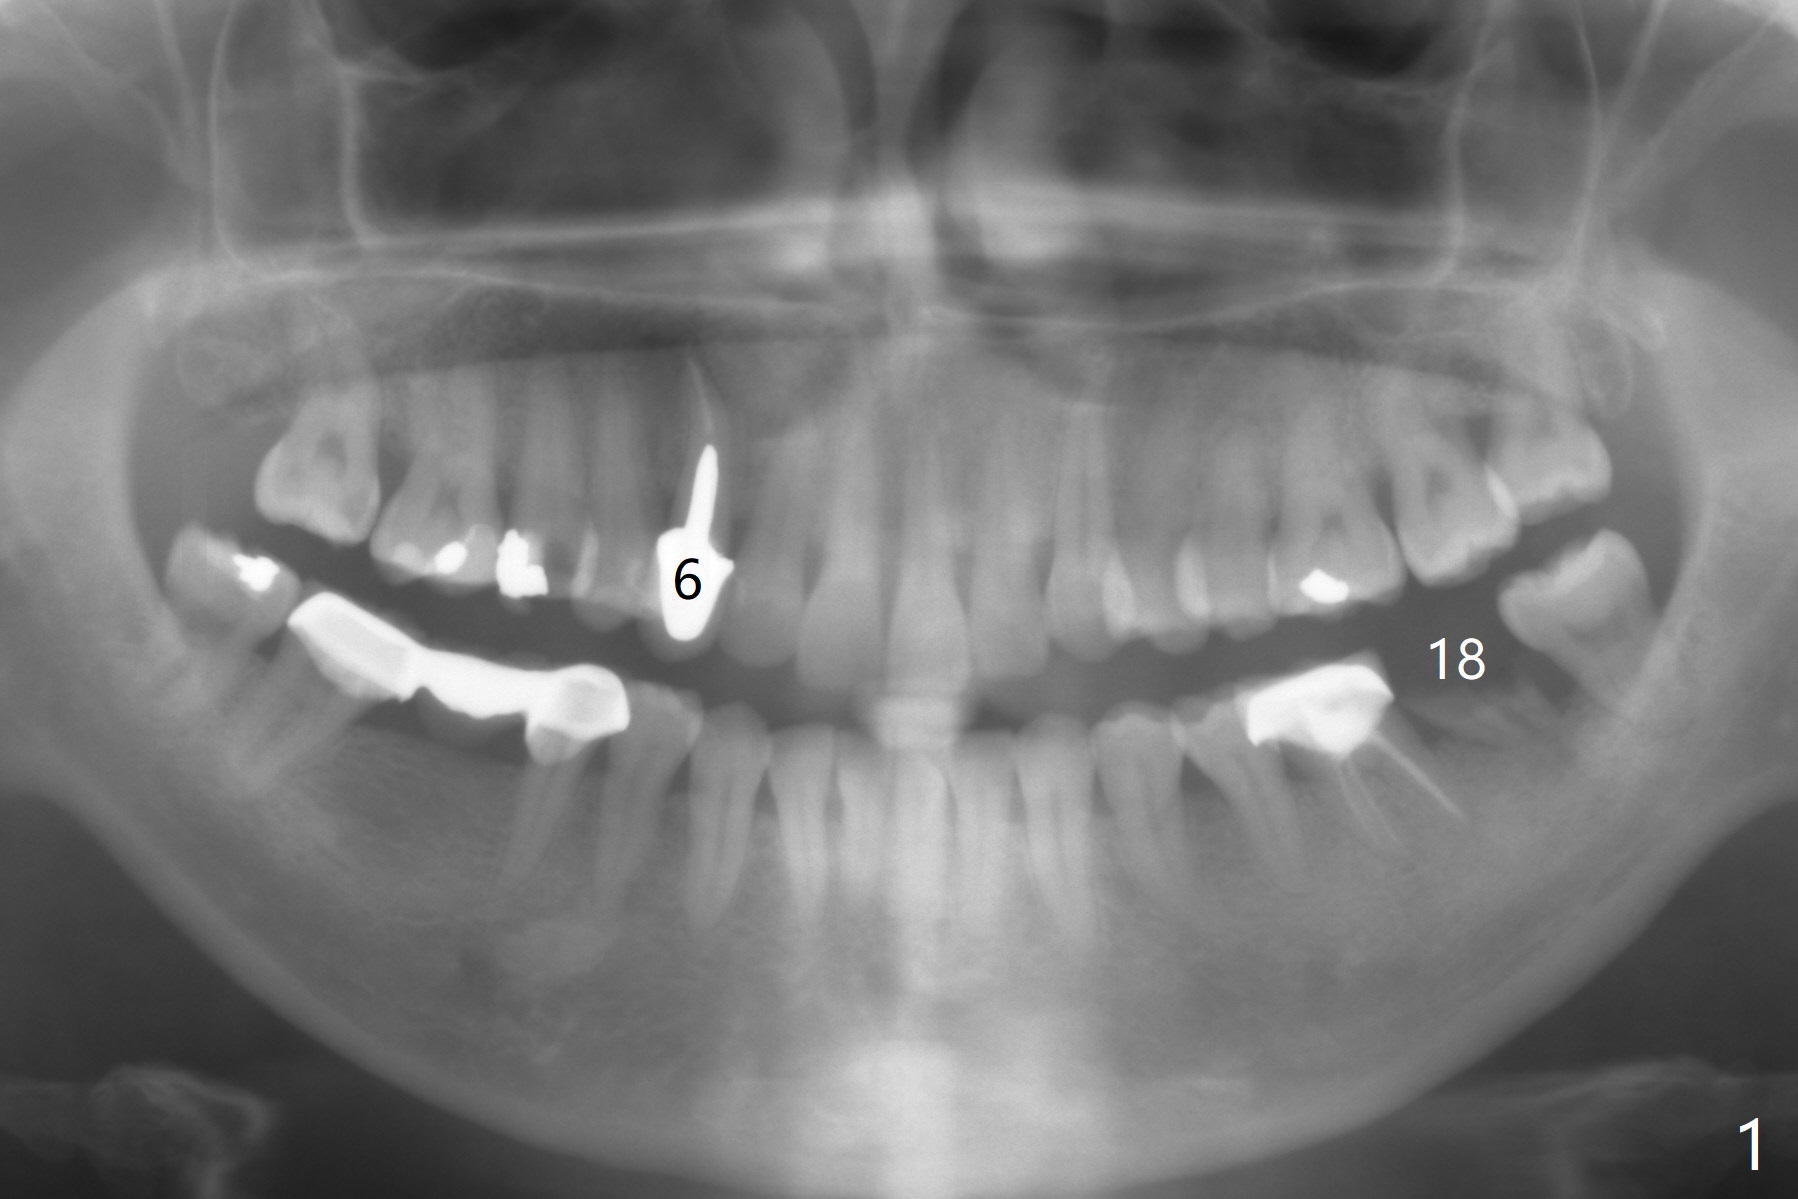

Curved Root

A 35-year-old woman has a loose tooth at #6, as related to the residual roots at #18 (Fig.1). Since the root curves distal, osteotomy will be initiated in the mesial slope (Fig.2) for 18 mm (gingival level). Proximity of an implant to a neighboring root may be associated with necrosis. Take PA and the final depth will be established for 18 mm (bone level) if indicated.